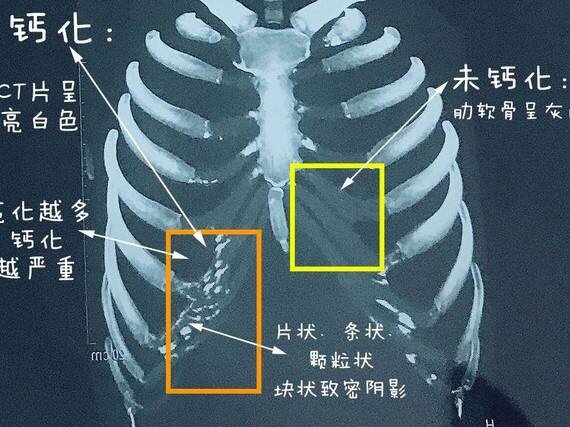

肋软骨钙化ct图片 第1页 图说健康

都说钙化的肋软骨不能做隆鼻 那什么是 新氧美容整形

肋软骨钙化 是怎么回事 怎么知道肋软 新氧美容整形

肋软骨钙化是什么 肋软骨钙化了是不是 新氧美容整形